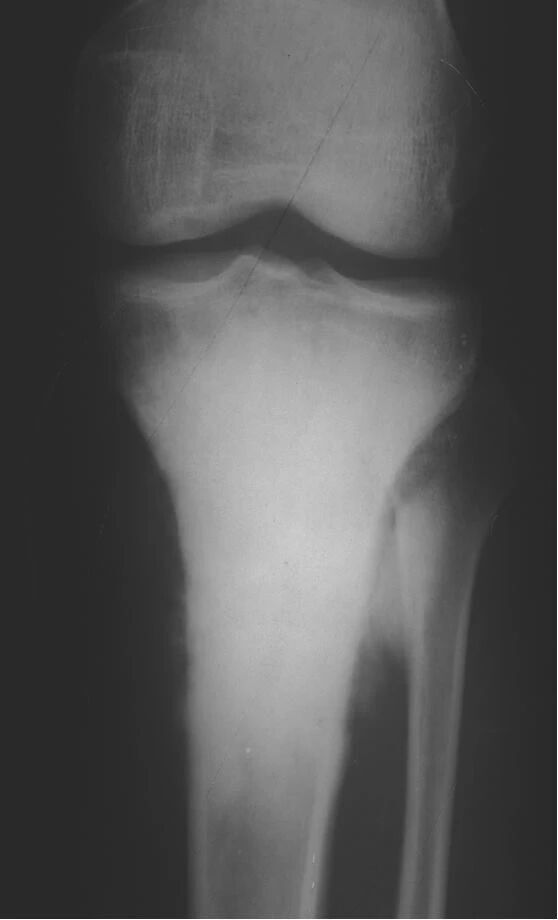

▌地图样破坏

地图样破坏是指肿瘤组织在一个局部呈团块状生长造成界限清楚的骨质破坏(图 1、图 2、图 3、图 4)。病灶可位于骨的中心或一侧部位,呈圆形、卵圆形密度减低区,与正常骨质分界清晰,边缘可有或无硬化带围绕,骨的形态无变化,病灶内可完全透亮或可见粗细不均、大小不等的残留骨嵴,内缘可光滑或呈分叶状压迹。地图样破坏见于大多数良性肿瘤和肿瘤样病变如单纯性骨囊肿、骨纤维结构不良、血管瘤等、也可见于部分恶性骨肿瘤如骨转移瘤、骨髓瘤等。

图 1.地图样破坏:单纯性骨囊肿